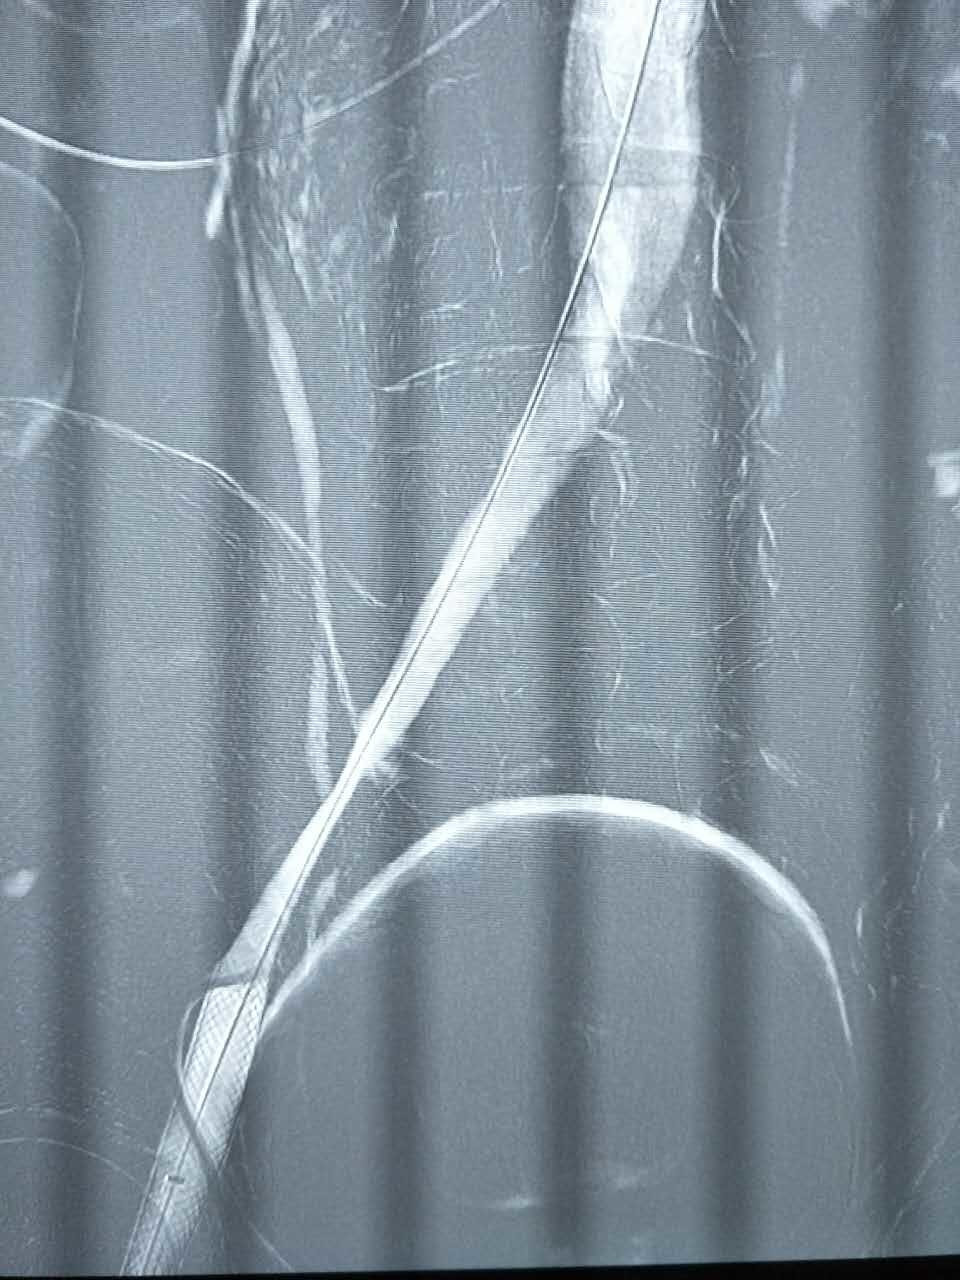

腿肿的原因分析

960x1280 - 123KB - JPEG